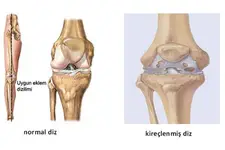

Diz Kıkırdak Belirtileri ve Tedavisi

Diz Kıkırdak Belirtileri ve Tedavisi Diz kıkırdağı, diz ekleminin düzgün çalışabilmesi için kritik bir yapı oluşturur. Kıkırdak, eklem yüzeylerini kaplayarak sürtünmeyi azaltır ve hareket sırasında şok emici bir görev üstlenir. Ancak, çeşitli nedenlerden dolayı diz kıkırdağında hasar meydana gelebilir. Bu yazıda, diz kıkırdağında oluşabilecek belirtiler, bu belirtilerin nedenleri ve tedavi yöntemleri detaylı bir şekilde ele alınacaktır. Diz Kıkırdak Hasarının Belirtileri Diz kıkırdağında meydana gelen hasar, çeşitli belirtilerle kendini gösterebilir. Bu belirtiler, hasarın ciddiyetine ve nedenine bağlı olarak değişiklik gösterebilir. Yaygın belirtiler şunlardır:

Diz Kıkırdak Hasarının Tedavi Yöntemleri Diz kıkırdak hasarının tedavisi, hasarın ciddiyetine ve bireyin genel sağlık durumuna bağlı olarak değişir. Tedavi yöntemleri arasında şunlar bulunmaktadır:

Sonuç Diz kıkırdak hasarı, bireylerin yaşam kalitesini olumsuz etkileyen önemli bir sağlık sorunudur. Belirtilerin erken tanınması ve uygun tedavi yöntemlerinin uygulanması, diz sağlığını korumak adına son derece önemlidir. Sağlıklı bir yaşam tarzı benimsemek, düzenli egzersiz yapmak ve aşırı kilodan kaçınmak, diz kıkırdak sağlığını korumada yardımcı olabilir. Ekstra Bilgiler Diz kıkırdak sağlığını korumak için aşağıdaki önlemler de dikkate alınabilir: